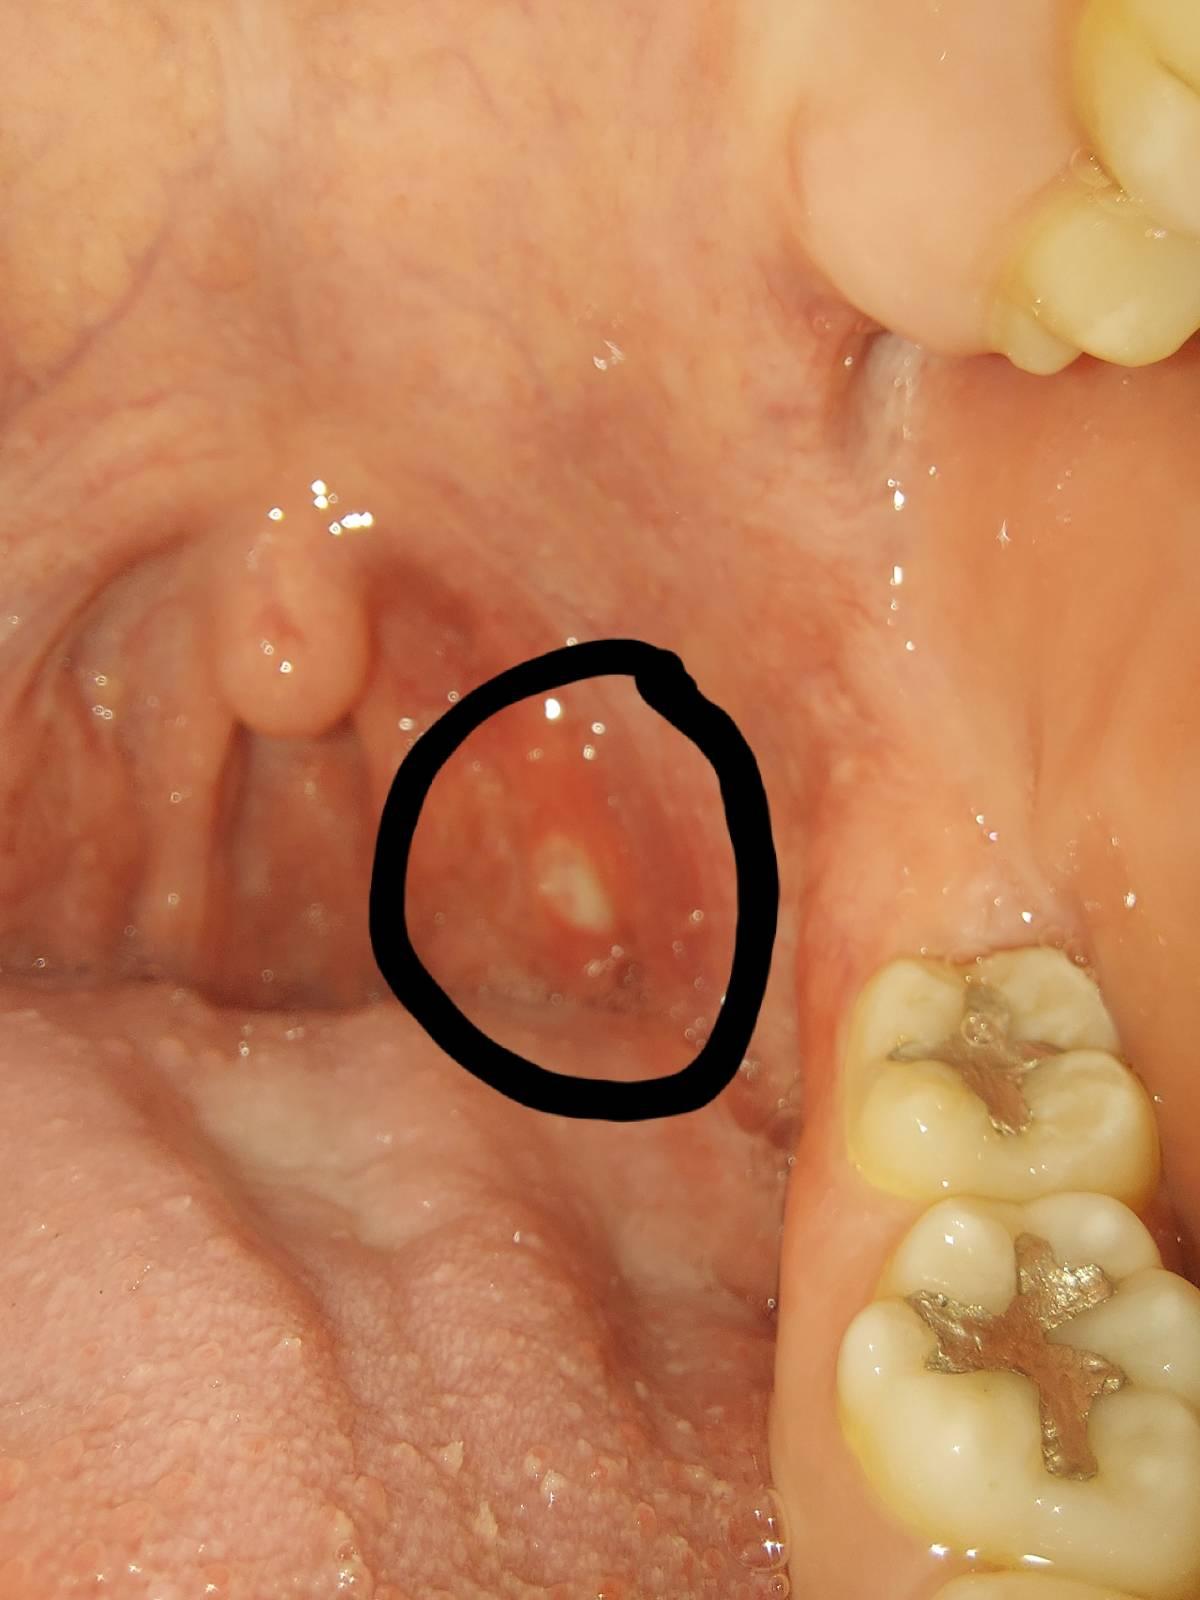

มีแผลที่ต่อมท่อมซิล คล้ายเป็นร้อนใน

เป็นแผลที่ต่อมท่อมซิล คล้ายๆกับเป็นร้อนใน

เวลากินอะไรเข้าไปก็เจ็บก็กินยาก มีวิธีรักษาไหมครับกรือควรไปพบหมอ มีรูปประกอบ